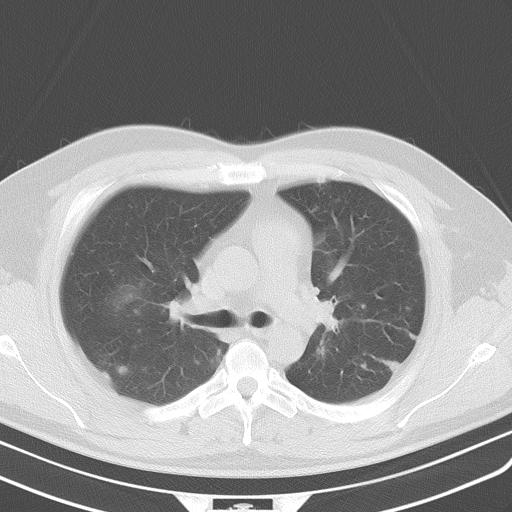

患者男性 35 主因发热咳嗽四天,血象不高,心肺听诊未见异常,无其它病史及传染病接触史。

两肺散在大小不等小结节影,下野较多,纵隔淋巴结增大。考虑:1、慢性血播性肺结核;2、霉菌病?3转移瘤待排。

两肺多发结节,部分病灶边缘不清,且示毛玻璃影。分布特点为沿血管支气管分布。

结合临床考虑;1,炎性肉芽肿性病变;霉菌?过敏性肺炎?2,韦格氏肉芽肿。3,转移瘤。

双肺多发散在结节影,部分边界不清,延支气管分布;纵隔内多发小结节(淋巴结)影...

考虑

1.双肺转移ca及纵隔淋巴结转移;

2.特殊类型感染(霉菌)?

3.韦氏肉芽肿?